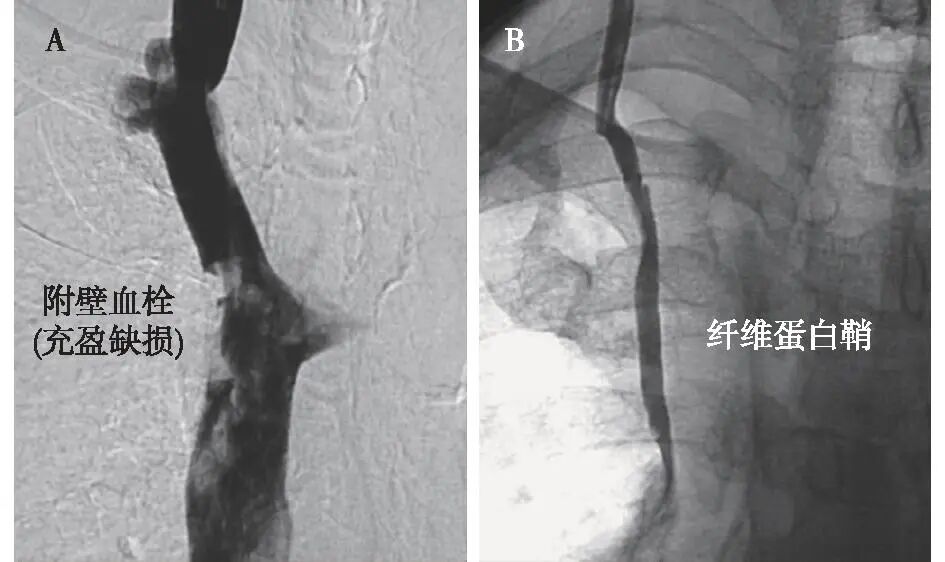

数字减影血管造影(DSA) DSA能够提供高分辨率、实时动态的血管影像,清晰地显示血管腔内的充盈缺损,是诊断CRDVT的金标准[22]。DSA下直接导管造影有助于确诊导管纤维蛋白鞘,造影剂在导管与纤维蛋白鞘间隙以及鞘与静脉壁间隙流动,形成两条平行的轨道状致密影;当造影剂从导管尖端流出时,不是呈正常喷射状弥散,而是沿纤维蛋白鞘内表面逆向反流一段距离,再进入腔静脉,形成像鼠尾一样的拖尾现象。导管缓慢回撤造影有助于鉴别血栓与纤维蛋白鞘。例如,对于上腔静脉的病变通过造影可以观察到附壁血栓引起的血管腔充盈缺损;此外,导管回撤造影能够清晰地显示出纤维蛋白鞘的轮廓(图3)[23]。DSA可能增加重症患者造影剂肾病风险,在需要更换导管、放置滤网、溶栓等治疗时,DSA可作为诊疗优选。

图3   上腔静脉数字减影血管造影检查图像[23]

A:血管腔内充盈缺损提示附壁血栓形成;B:中心静脉导管回撤后见纤维蛋白鞘